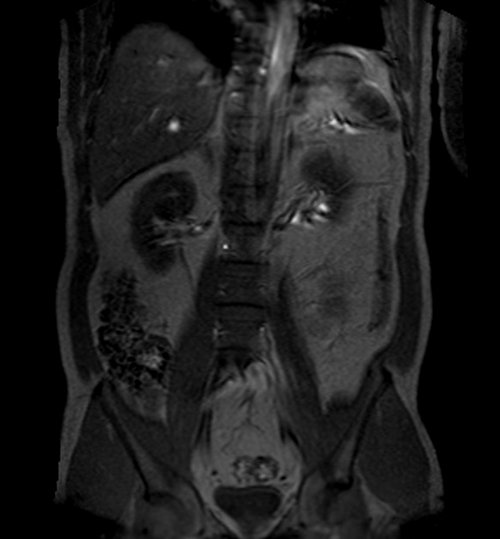

mra abdomen localizer 3 - MRI